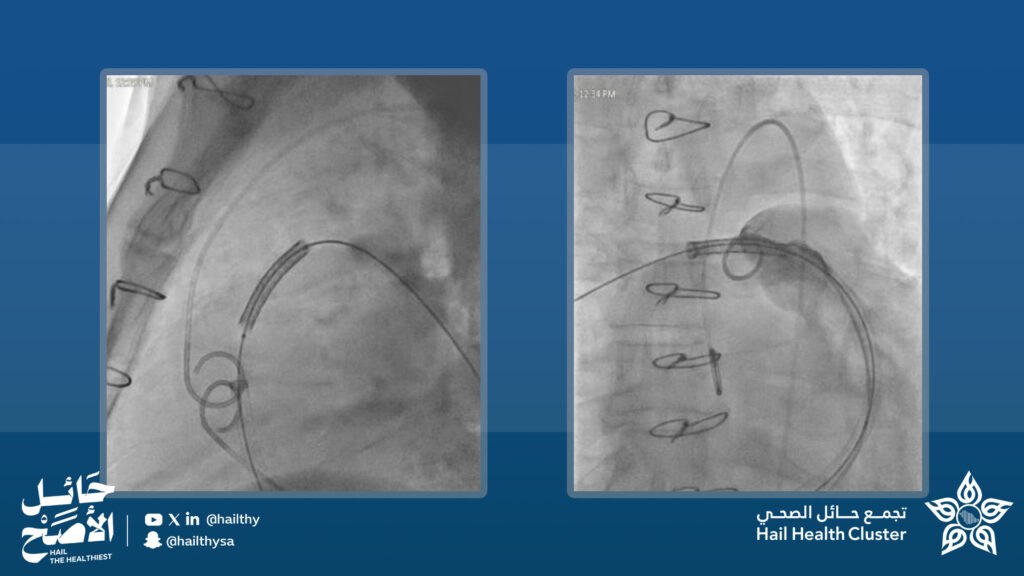

نـــجــح مــركـز الـقــلــب فـــي مـــســتــشــفــى الــمـلـك سلمان الـــتــخــصــصــي بــحـــائــل فــي إجــراء أول عــمــلــيـة من نوعها بالمنطقة لزراعة صمام رئوي عبر القسطرة لمريض في العقد السادس من العمر ، باستخدام صمام رئوي بديل تم تركيبه عبر الوريد الفخذي. ويعكس هذا الإنجاز قدرة الكوادر المحلية على تطبيق أحدث التقنيات لخدمة المرضى ذوي الخطورة العالية.

أُجريت العملية تحت التخدير العام وباستخدام تصوير متقدم لضمان الدقة، مع تجهيز القناة وزرع دعامة حــديـثـة وتــوســيـعـهـا ببالونات عالية الضغط. ويعزز هذا الـــنـــجـــاح مــكــانـــة مــــركــز الـقــلــب كـــوجــهـة مـتقدمة لـعلاج أمــــراض الـــقـلـب الـتـداخـلـــيــــة.